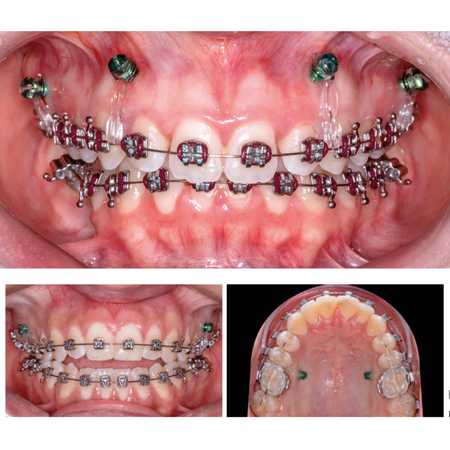

Desafios no tratamento de pacientes com discrepâncias verticais: abordagens clínicas com mini-implantes

INTRODUÇÃO: Os pacientes adultos têm, cada vez mais, buscado tratamentos ortodônticos sem recorrer à cirurgia ortognática. Em alguns casos, sejam eles de mordida aberta anterior ou de mordida profunda, é possível usar mini-implan...

Cirurgia Ortognática Mordida Aberta Ancoragem Ortodôntica Intrusão Dentária Mini-implantes

Desafíos en el tratamiento de pacientes con discrepancias verticales: abordajes clínicos con microimplantes

INTRODUCCIÓN: Cada vez más pacientes adultos buscan tratamiento de Ortodoncia sin recurrir a la cirugía ortognática. En algunos casos, ya sea mordida abierta anterior o mordida profunda, es posible utilizar microimplantes para propor...

Microimplantes Cirugía ortognática Mordida abierta Anclaje ortodóncico Intrusión dental